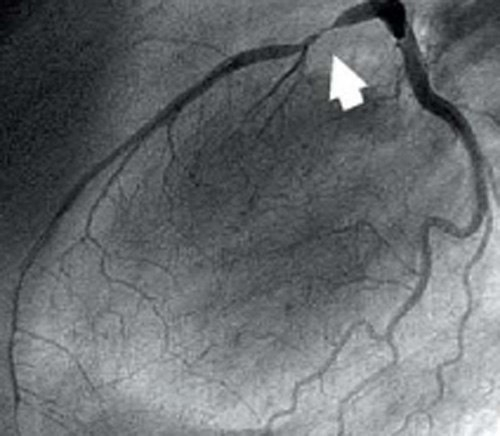

Коронарография на данный момент - золотой стандарт диагностики ИБС, поскольку ни одно другое исследование не позволит достоверно увидеть причину ИБС - стенозы (сужения) коронарных артерий. Вот так выглядят здоровые артерии:

А вот так: стенозы, вызванные бляшками:

Условно, принято считать, что значимым с точки зрения гемодинамики является уменьшение диаметра сосуда на 70-75%. Чем выше степень стеноза, тем выше вероятность того, что в зоне кровоснабжения этой артерии сердце испытывает кислородное голодание - ту самую ишемию.